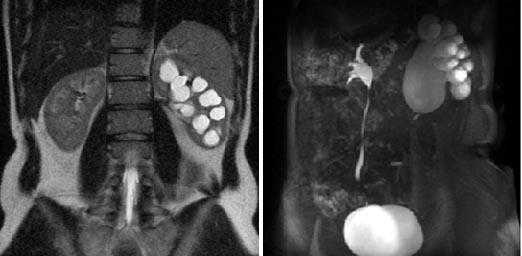

Левосторонний гидронефроз с дилатацией левой почечной лоханки. Пельвиуретральный переход заметно сужен, присутствует задержка выведения жидкости в левый мочеточник.

Гидронефротическая трансформация левой почки III ст, паренхима почки визуализируется в виде тонкого ободка, толщиной до 0,1-0,2 см, резко атрофична. Стеноз лоханочно-мочеточникового сегмента слева (хроническая обструктивная уропатия), (стрелка).

Выраженное расширение ЧЛС обеих почек, значительное расширение и S-образная извитость мочеточников с обеих сторон на фоне инфравезикальной обструктции при доброкачественной гиперплазии предстательной железы. Гиднонефроз правой почки II-III ст., левой почки II ст.